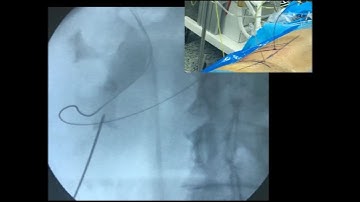

Percutaneous Nephrolithotomy - Tract dilation using Amplatz sheath